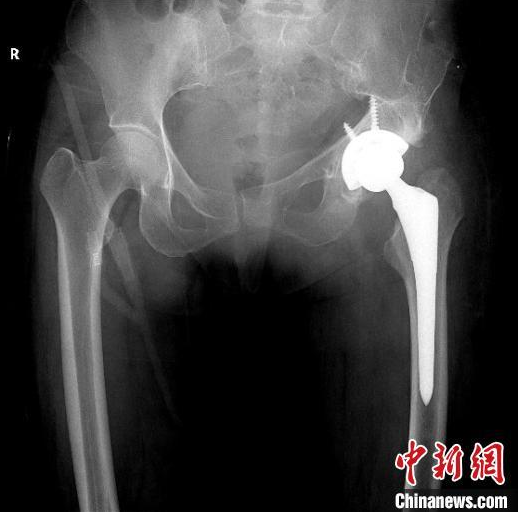

26年前的一场车祸,让患者邹阿姨(化名)身体经历了多处创伤,骨盆髋臼粉碎骨折、膀胱破裂,小肠破裂……那场车祸带来的除了身上刀痕累累的伤疤,还有当年手术造成的继发性严重股骨头坏死。二十多年来,邹阿姨一直忍受着股骨头坏死带来的疼痛。多年来,她辗转多地三甲医院求医都无法治疗。“疼得受不了的时候就自己打消炎针,缓解一点疼痛”,疼痛加重,行走入睡都困难时,邹阿姨就自己打针镇痛。近两年,邹阿姨因疼痛加重而无法行走,最后经人介绍找到南方医科大学中西医结合医院骨伤科黄刚主任。邹阿姨来院后经X线片及CT检查,发现左侧股骨头坏死、形态失常,已经脱离正常的位置,且很难找到真臼,左侧髋臼形态失常、部分骨质缺失。想要彻底解决邹阿姨的问题,需要进行左侧人工全髋关节置换。但邹阿姨患病二十余年,且有过失败的手术病史,手术难度系数较大,不能有任何偏差,稍有偏差,严重者可影响手术效果,留下后遗症。黄刚主任组织科室多次讨论,并及时与患者及家属沟通,决定依靠先进的3D打印技术,为患者进行术前规划,精准定位真臼,量身定制进行精准手术治疗方案。黄刚主任首先为邹阿姨进行了CT扫描,将邹阿姨双髋关节CT扫描数据传输到3D打印机,按照1:1的比例用3D技术“打印”了一个一模一样的髋关节模型。该模型将邹阿姨的坏死关节及脱位程度和其他细节完美呈现。黄刚主任首先为邹阿姨进行了CT扫描,将邹阿姨双髋关节CT扫描数据传输到3D打印机,按照1:1的比例用3D技术“打印”了一个一模一样的髋关节模型。该模型将邹阿姨的坏死关节及脱位程度和其他细节完美呈现。手术历时2个多小时,出血200ML,顺利地为邹阿姨进行了左侧人工全髋关节置换术,将人工髋关节准确地安装在邹阿姨的真臼内并做了牢固的固定。术后第4天邹阿姨就已下地行走。

根据CT数据打印出3D模型,实现精准置换